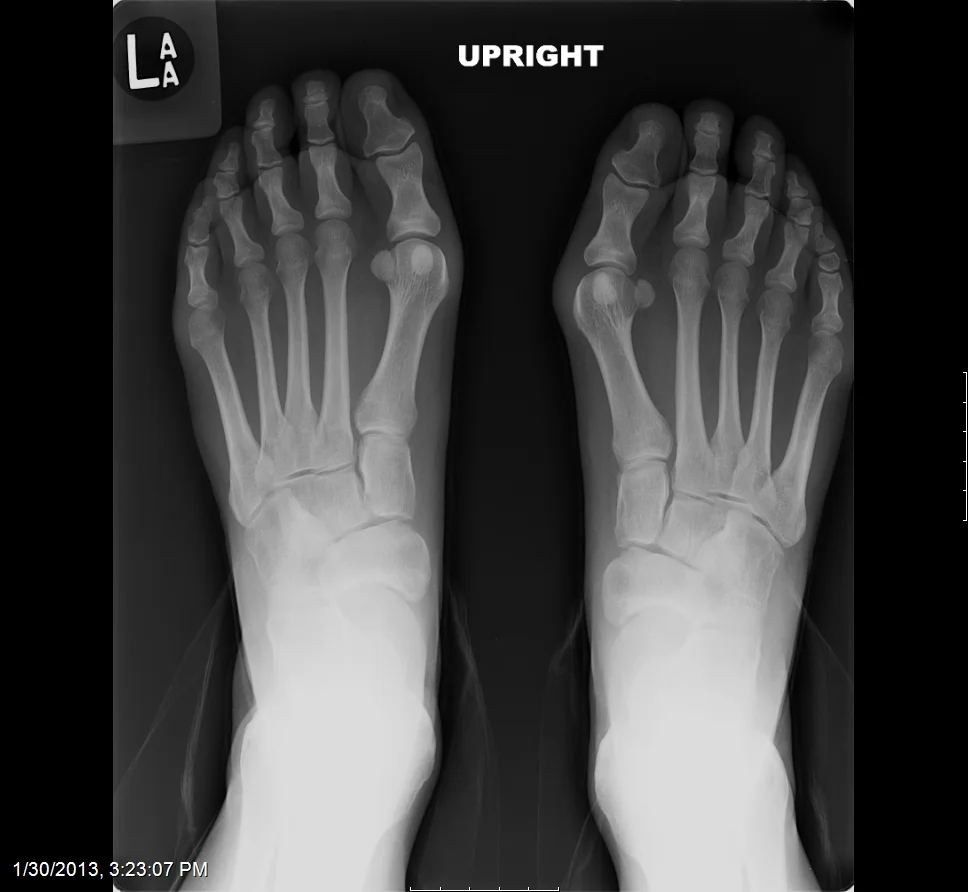

Example Bunion Surgery Before & Immediate Post-Op. Individual results may vary.